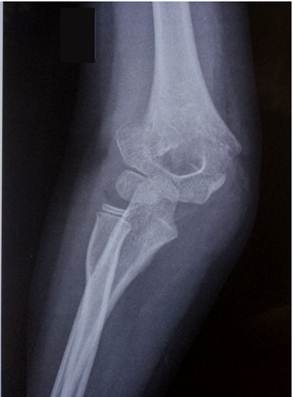

Область локтя в разном возрасте

Василий Оскарович Маркс говорил, что неподготовленный человек на

снимке локтевого сустава здорового ребенка найдёт восемь переломов. Очень даже

может быть – рентгенологическая картина локтя ребенка в возрасте от года до

четырнадцати лет насыщена ядрами окостенения и зонами роста, которые легко

принять за костный отломок или осколок, особенно если в анамнезе есть травма.

11- 13 лет

Это возраст, в котором все ядра окостенения достигли максимального

развития и приняли формы соответсвующих образований. На рентгенограммах их

разделяют узкие полоски ростковых зон. Это максимальный расцвет детского локтя.

Возраст

12 лет. Все ядра окостенения локтя развиты и разделены узкими хрящевыми

прослойками. Вершина локтевого отростка содержит основное ядро окостенения и

ядро – спутник неправильной формы.

14 лет. Стремительное закрытие зон роста локтевого сустава. Можно заметить

узкие просветы в основании медиального и латерального надмыщелков, а также пока

еще открытую зону роста в локтевом отростке.